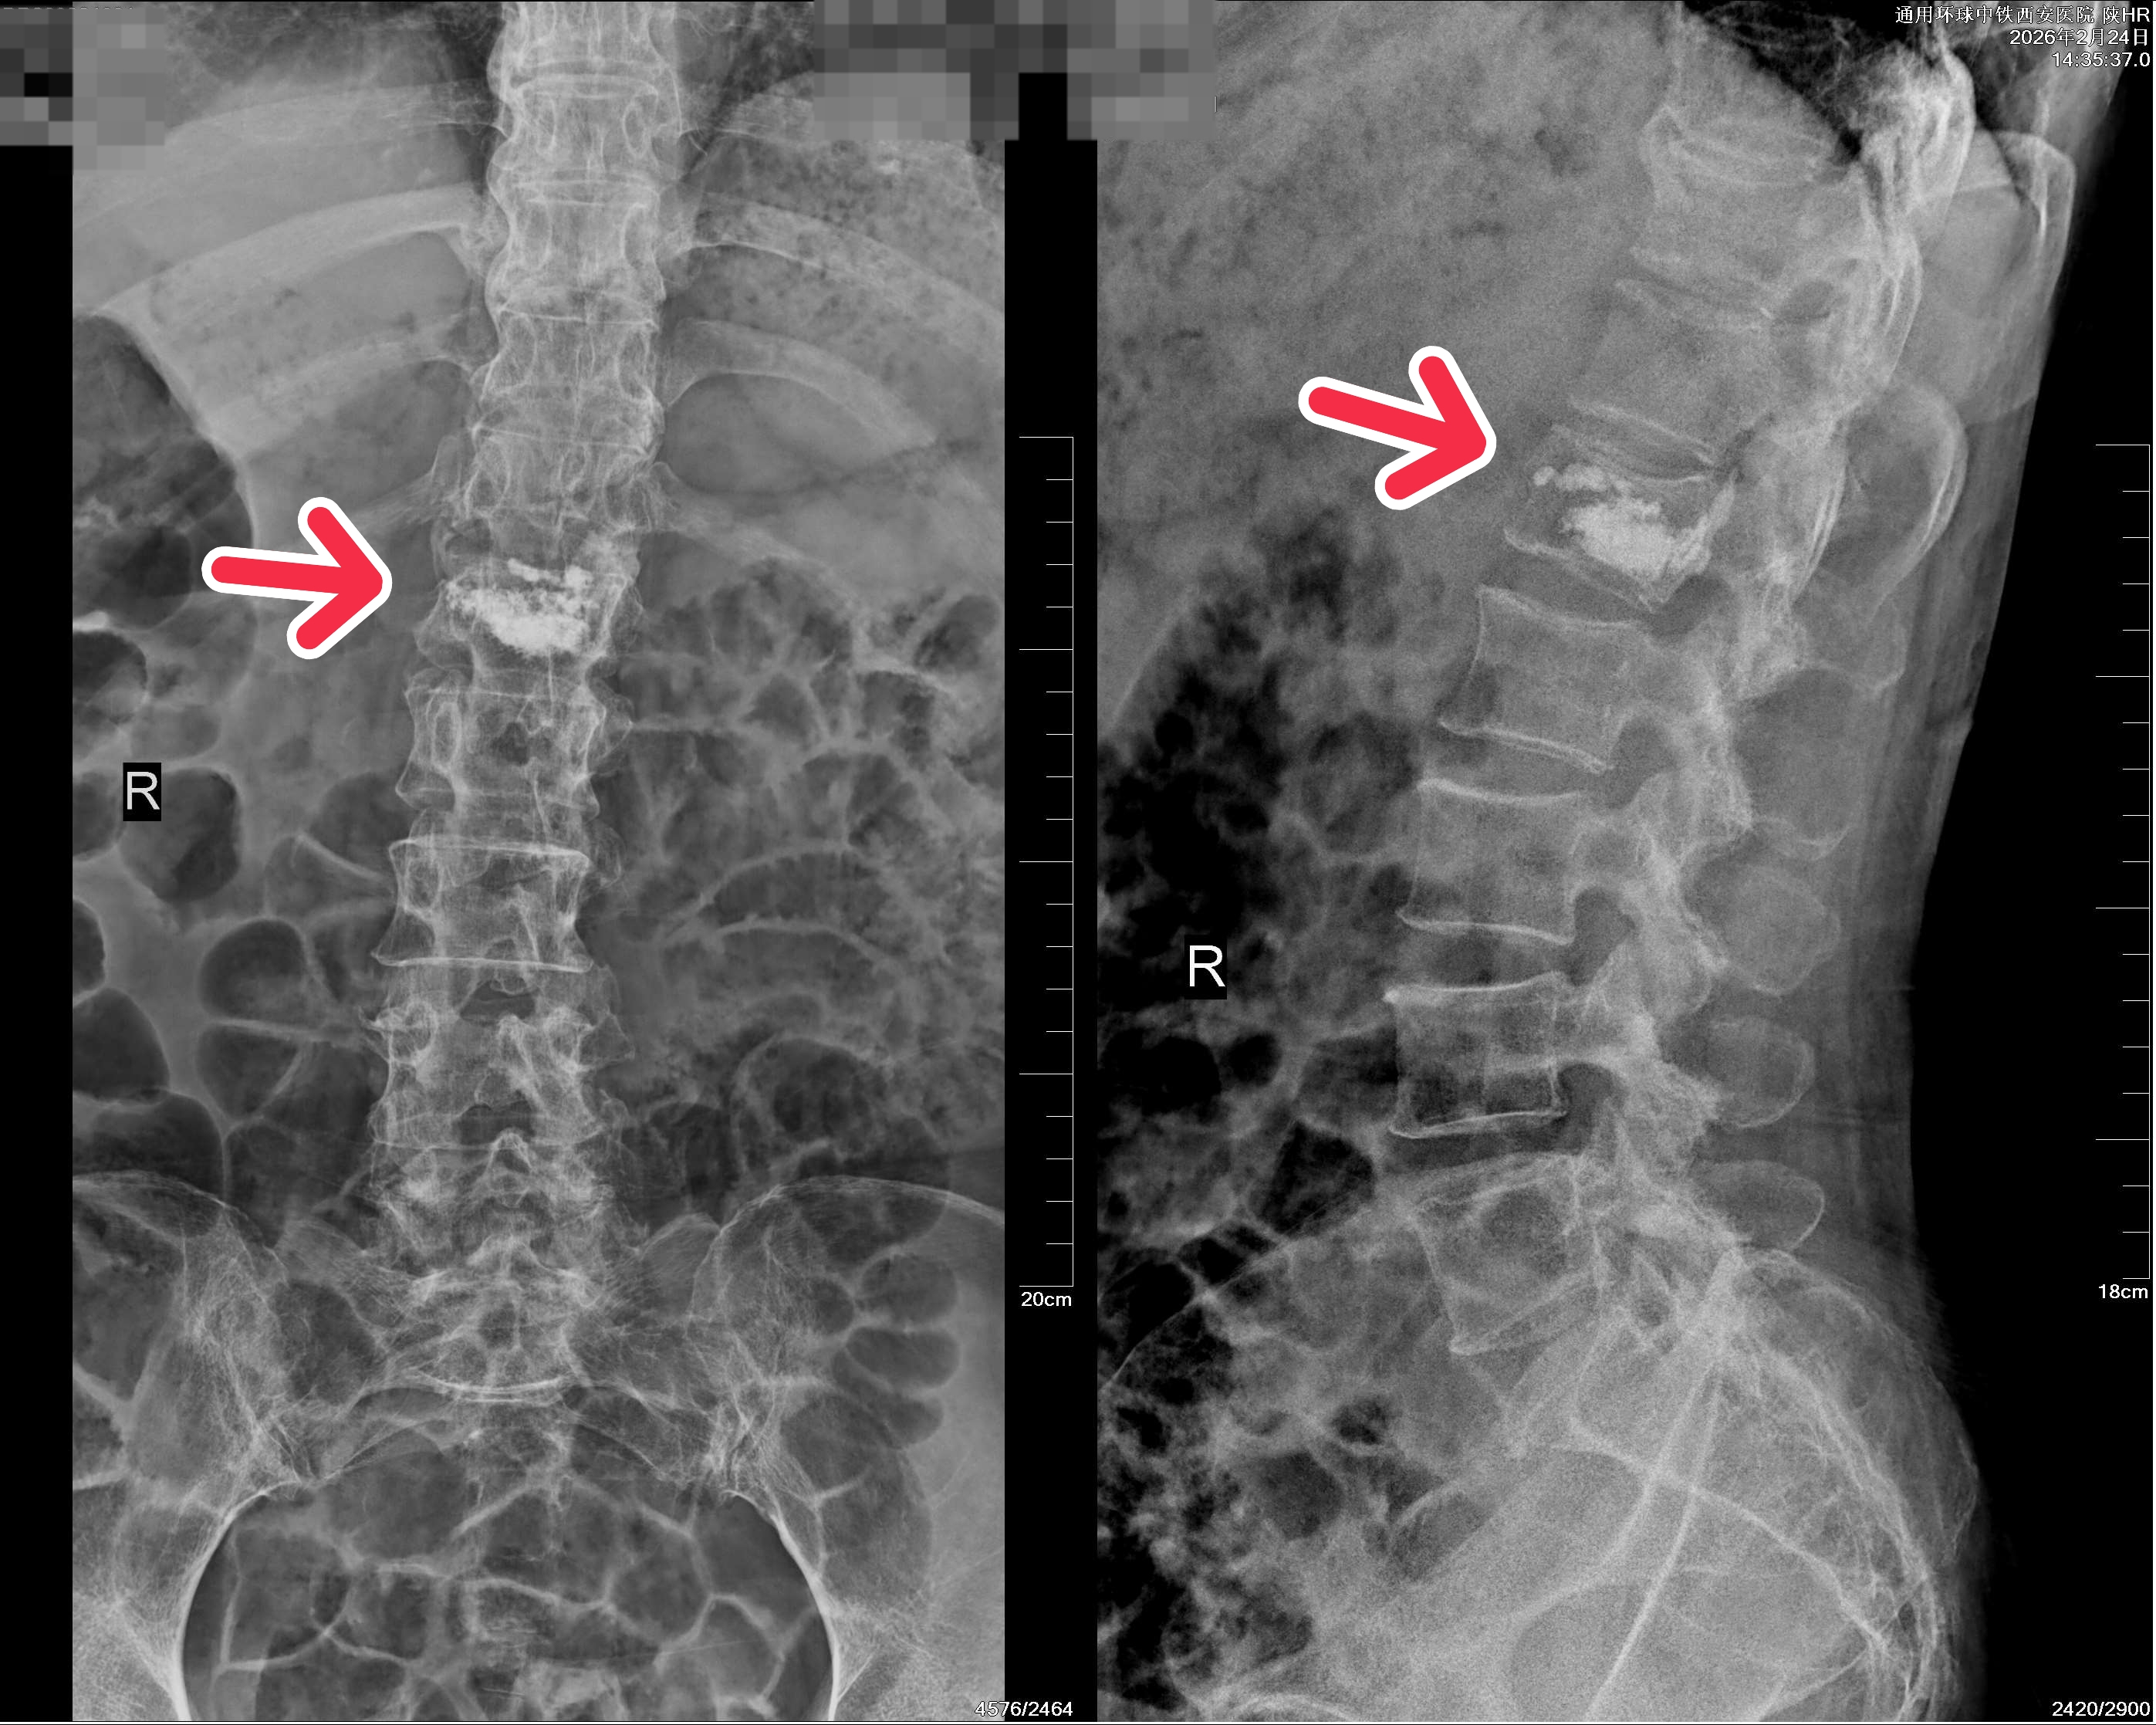

上:术前 / 下:术后

患者血压较高,姬传磊主任团队术前请心血管病院副院长何丽会诊,并制定了周密的手术方案及应急预案。手术团队凭借丰富的经验和娴熟的技术,为患者成功实施了腰1椎体压缩性骨折椎体成形术。

在医护团队的悉心照料下,患者术后次日便可佩戴腰围坐立和下床活动,腰背部疼痛显著缓解,患者及家属对手术效果表示满意,并对姬传磊主任及全体医护人员的精湛医术和贴心服务表达了诚挚谢意。